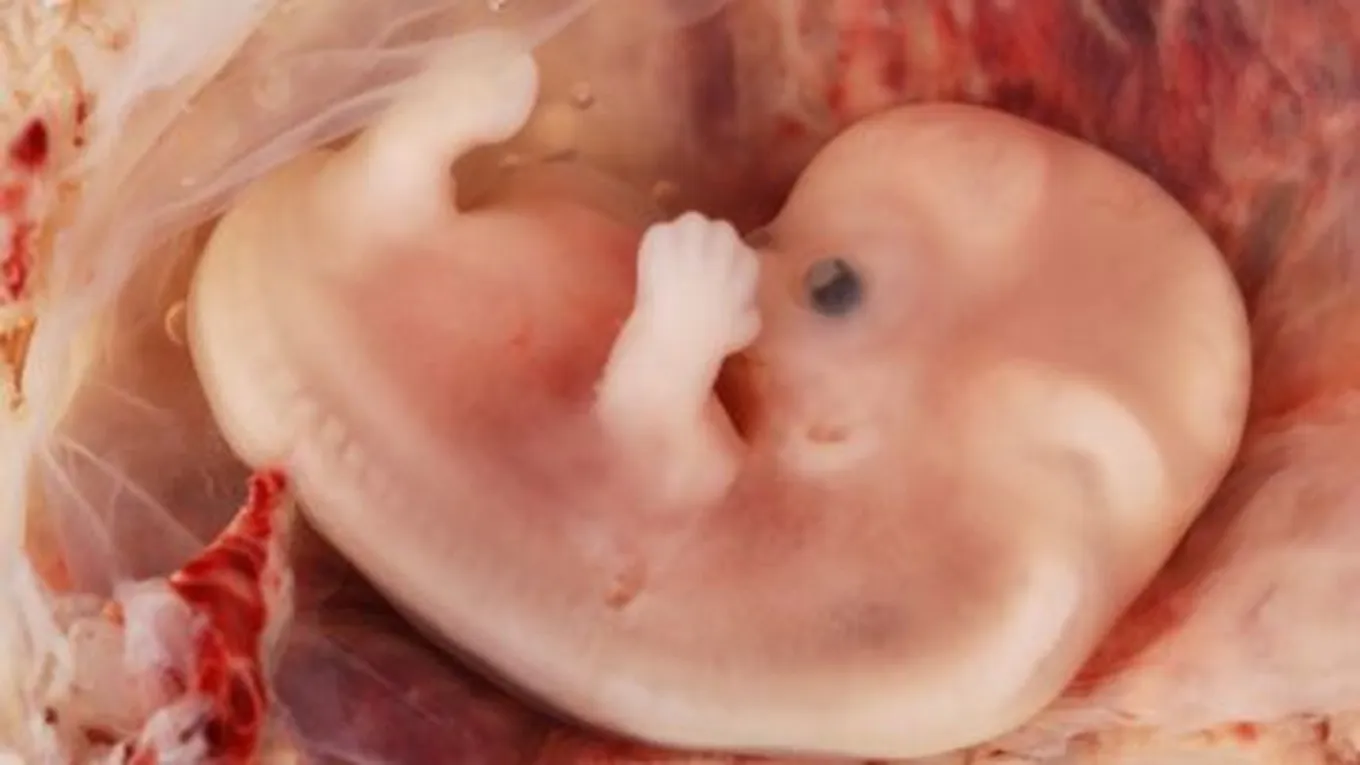

يبدأ من تخصيب البويضة إلى الأسبوع الثالث عشر من الحمل، حيث يمتلئ فيه كيس الحمل تدريجياً بالسوائل التي تحيط بالجنين لحمايته، وتتطور المشيمة بشكل تدريجي حتى تصبح دائريّة الشكل لنقل المغذيات إلى الطفل وإخراج الفضلات والأوساخ من محيط الطفل، وينمو الطفل خلال هذه الفترة حتى يصل بآخر الشهر الأول إلى ربع بوصة أي أصغر من حبة الأرز.

يستمر الجنين بالنمو، وتبدأ الأطراف الخارجية بالنمو، وتتشكل العيون، ومن أهم التطورات التي يمر بها الجنين هو نمو الأنبوب العصبيّ الذي يتكوّن من الدماغ، والحبل الشوكي، والأنسجة العصبية الأخرى التي تشكل الجهاز العصبي المركزي، ويكون الرأس أكبر من الجسم خلال هذه الفترة، ويصبح طول الجنين بوصة واحدة، ويبدأ قلبه بالنبض، وتكون أطرافه ظاهرة بشكل كامل وأعضاؤه التناسلية تتطور، وطوله في نهاية الثلث الأول يصل إلى أربعة بوصات.